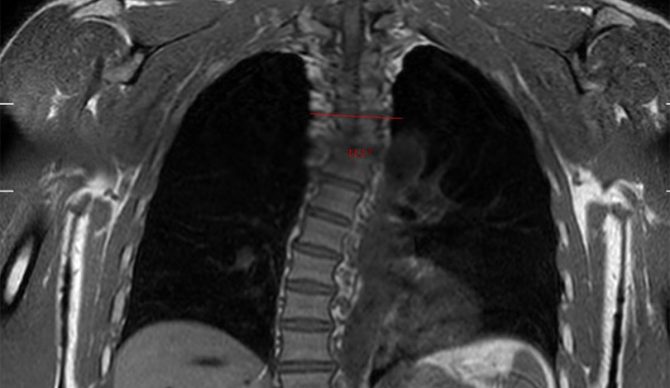

“I had a recent body scan done at @prenuvo to get a rundown of all the potential health concerns I know about and want to check in on or am unaware of and need to address now that I’m off tour and have some downtime,” he wrote on Instagram. As you can read, I had a few minor and moderate findings to address which I won’t go over here. Clearly my scoliosis, which I’ve spoken about many times, is a serious issue but there were a few things I was unaware of that I reviewed with their doctor to either deal with or keep in mind as I continue future scans and see any noticeable changes.”

That back problem has been with him for a long time, so he’s gotten pretty used to managing it by now. “I am carrying a pretty serious back problem,” he said all the way back in 2016. “I have been for a number of years now. I don’t know if I’ve been in denial of it or pretending it’s not as bad as it is or whatever, but I have quite a lot of days where I don’t actually surf because my back hurts. It’s the lower back. I get scoliosis pretty badly in my back, and I’ve got a real imbalance where I’m short on one side and long on the other. Then up the middle back it sort of goes the opposite – I’ve got this s-curve in my back.”

The s-curve he was talking about nearly a decade ago is clearly visible in the Prenuvo scan you see here. Although he’s spoken in depth about it before, it felt strange to him to show it to the world in black and white. It is, however, important to acknowledge the fact that we all age, and Kelly’s willingness to do so will, somewhat ironically, likely slow down the process a bit.

“Showing my spine feels super personal as it’s crazy to see the curvature I’ve dealt with all these years but I think it’s important people know we all deal with physical ailments and can find ways to minimize their impacts and potentially reverse what comes up,” he continued. “These scans are especially important for people in their 50s and beyond and I’m super thankful Prenuvo were able to find me a time in the short window I had to make it into their clinic.”